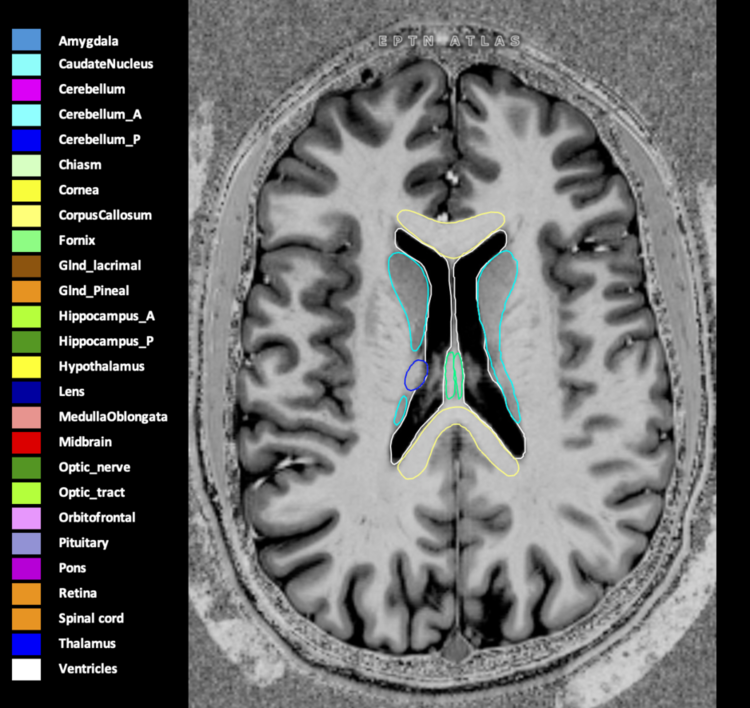

Included are all OARs known to be relevant for radiation-induced toxicity in neuro-oncology: brain, brainstem (midbrain, pons, medulla oblongata), chiasm, cerebellum (anterior & posterior), cochlea, cornea, hippocampus (anterior & posterior), hypothalamus, lens, lacrimal gland, optic nerve, pituitary, skin, and vestibular & semicircular canals. To further facilitate research on cognition, vision and radiological changes after irradiation of the brain, potential clinically-relevant OARs are included: amygdala, caudate nucleus, cerebellum (anterior & posterior), corpus callosum, fornix, macula, optic tract, orbitofrontal cortex, periventricular space (PVS), pineal gland, and thalamus.

Three-dimensional delineation of the 25 consensus OARs for neuro-oncology are shown on CT (WW/WL 120/40, 3000/600), 3T MR images, (T1Gd, T2FLAIR 1mm) and 7T MR (MP2RAGE 0.7 mm). All are presented in transversal, sagittal and coronal view.